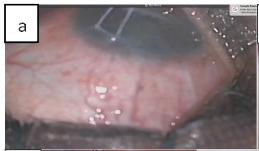

Most glaucoma surgeries were done by AO, few by GIN during surgical training under direct supervision. Three were done by other surgeons during a symposium surgical skill transfer in 2019. There are basically 14 steps in the technique. Corneal traction with 6/0 vicryl after the routine cleansing draping and eyelid opening with speculum.

Fornix based conjunctival peritomy to include superior and lateral rectus muscles, or temporal and inferior or medial and inferior or medial and superior for supero-temporal, infero-temporal, inferonasal, supero-nasal placement of the implant respectively.

The tubes were primed with Balanced Salt Solution (BSS) to ensure patency avoiding touching the valve in AGV. The Baervedlt, ADDI and ACP were ligated with 7/0 vicryl absorbable suture to stop the flow of aqueous through the tube before a capsule is built around the plate. This is confirmed by flushing the tube after tying off to ensure complete blockage. ACP had 5/0 nylon ripcord in the lumen.

Blunt dissection was extended posteriorly separating tenon capsule from the sclera using the Westcott and conjunctival forceps.

The plates were secured at 8mm or 9mm from the limbus with 9/0 or 10/0 nylon sutures.

The wings of the ADDI and Baerveldt and clear path 350 were tucked under the rectus muscles. Paracentesis was created with 150 and a 23gauge needle was used to tunnel into the anterior chamber, viscoelastic or BSS was used to prevent shallow anterior chamber.

The tubes were trimmed bevel up at mid iris length or 2mm into cornea and threaded through the scleral tunnel parallel to the iris plane using a tube inserter or tyer.

Tubes were covered with scleral or cornea graft and secured with 10/0 suture.

Conjunctiva closed water tight with 8/0 vicryl suture. Anterior chamber depth checked to ensure that tube was free from the iris and cornea. Subconjunctival injection of Genticin and Dexamethasone, Maxitriol ointment applied,

speculum removed and eye padded and covered with Fox shield till following day. (1-day post-op)